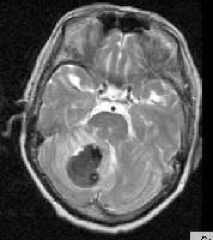

МРТ головного мозга. Аксиальная Т2-взвешенная МРТ. Кровоизлияние в мозжечок.